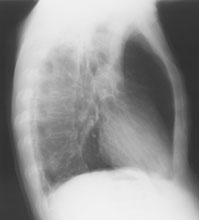

Ein 71-jähriger Italiener beklagt sich über einen reduzierten Allgemeinzustand und subfebrile Temperaturen. Er raucht seit 45 Jahren.

Husten und Auswurf hätte er immer gehabt, berichtet der Patient. Mit der Frage nach einem Infiltrat wird ein Röntgenbild verordnet:

Thorax seitlich

Bild vergrössern

Welche Befunde imponieren (mehrere richtige Antworten möglich)?